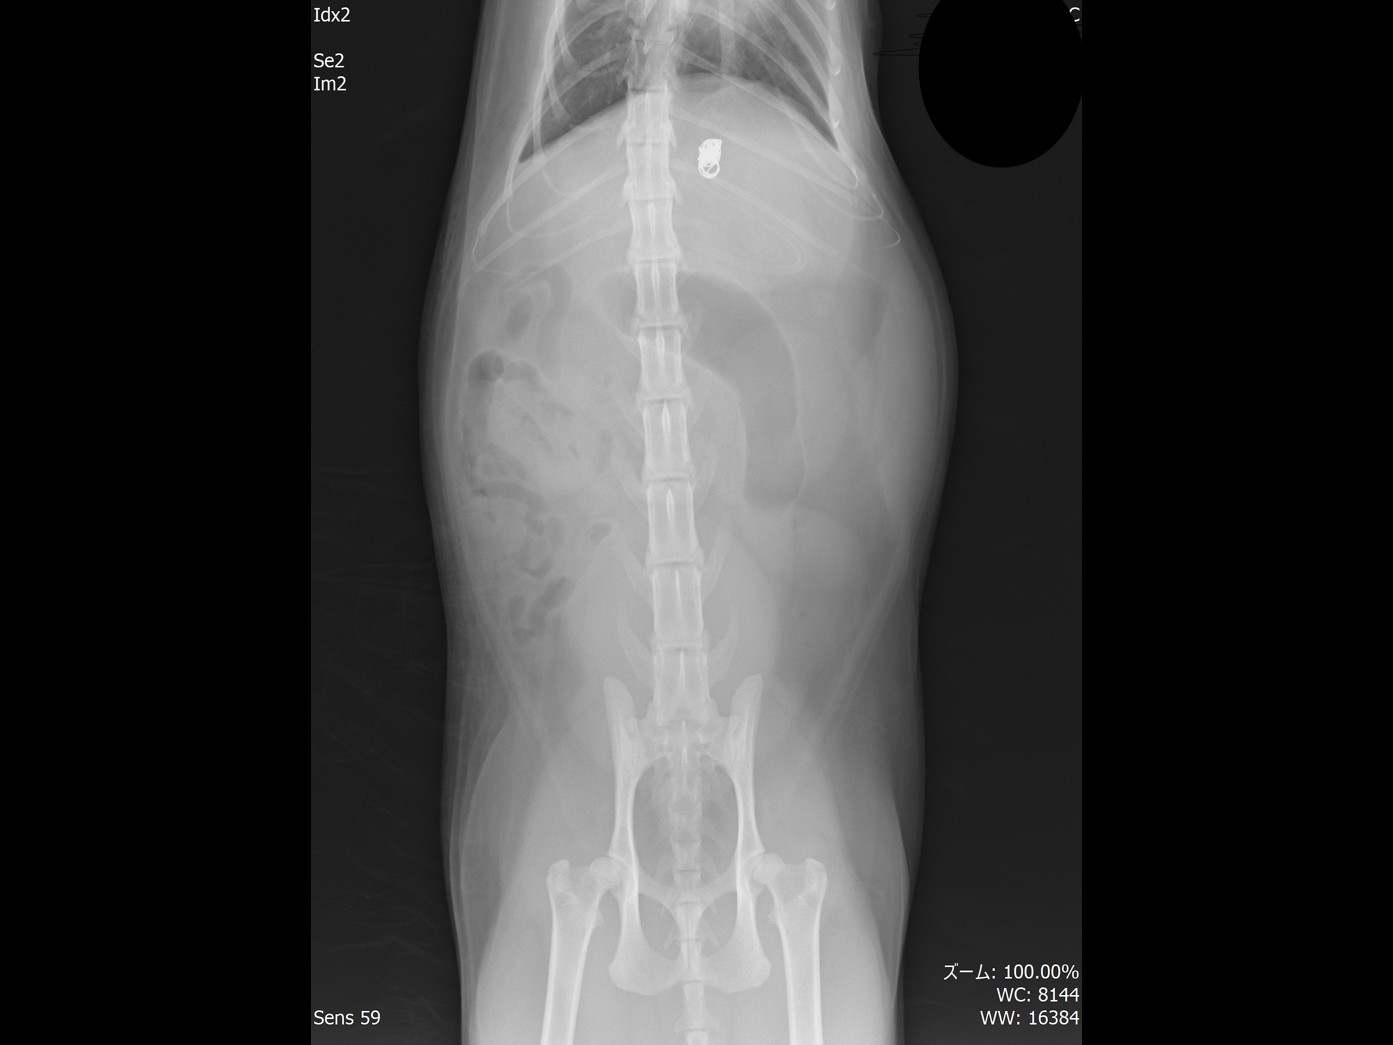

術後のレントゲン画像